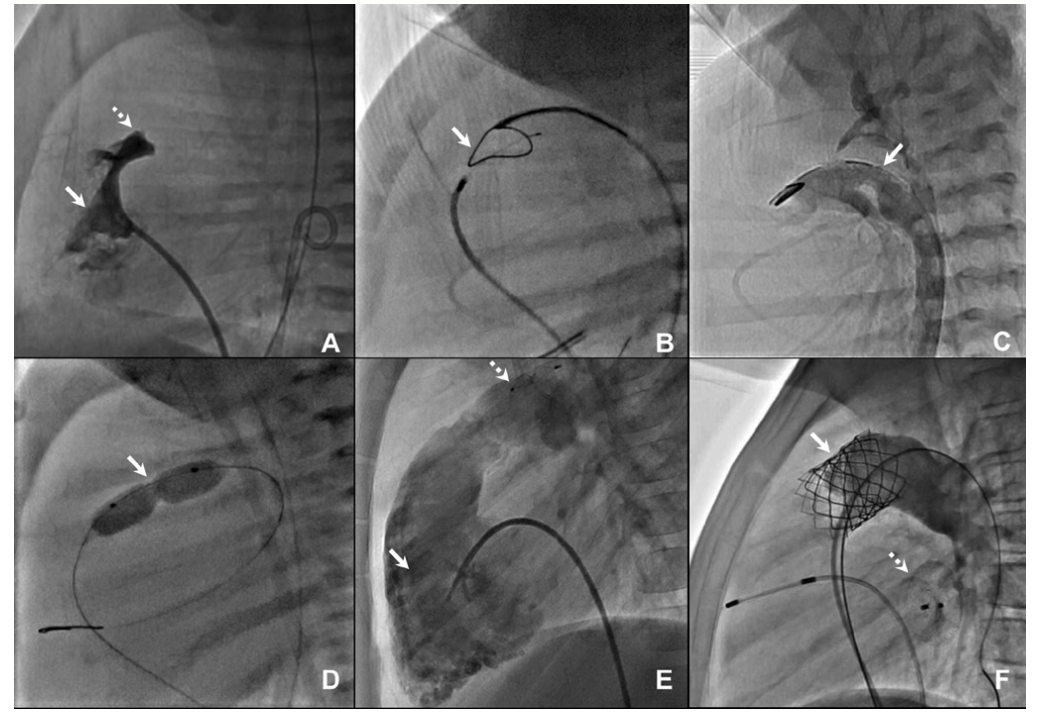

Regardless of prior catheterization or surgical management strategies, a total of 9 patients (60%) had a TPV placed (Table 3). The median age and weight at TPV placement for these patients was 6 years (range, 4-8) and 19.7 kg (range 17.1-26.4). The most common indications for TPV were moderate to severe pulmonary insufficiency, mild to moderate RV dilation, and exercise intolerance. TPV was successfully implanted in all 9 patients (100%) without major complications. Transient ventricular ectopy was seen in 2 patients (22%), both of whom were placed on nadolol. No recurrence was seen, and the medicine was discontinued as an outpatient in both instances. One patient (11%) developed femoral vein thrombosis on the side used to advance the TPV, which required anticoagulation and repeat catheterization for stenting of the femoral and iliac veins.

Median length of follow-up after TPV placement was 3.4 years (range, 0.3-5.3). All 9 patients (100%) had a functional TPV and were clinically doing well at their latest visit. The degree of pulmonary insufficiency on most recent echocardiogram was trivial or mild in 7 patients (78%) and moderate in 2 patients (22%). All 9 patients (100%) had freedom from bacterial endocarditis. The 6 remaining patients are future potential TPV candidates if indicated.